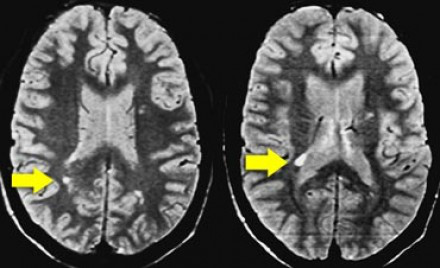

多發(fā)斑塊狀病灶的鑒別診斷

圖片一

在上圖中,是各種多發(fā)性點狀和斑塊狀白質(zhì)病灶圖像,我們對其中部分病例進行詳細討論。需要說明的是,以下鑒別診斷中提到的疾病與上圖中的圖像并不完全重合。

交界區(qū)腦梗死

MRI成像病灶要點:一般來說,這些病灶僅位于一個腦半球,要么位于深層白質(zhì)與灰質(zhì)的分水嶺區(qū)域(watershed area),要么位于周圍的分水嶺區(qū)域。在上圖中,病灶位于深層的分水嶺區(qū)域。

急性播散性腦脊髓炎(ADEM)

MRI成像病灶要點:在感染或接種疫苗后10-14天,多個局灶性病灶出現(xiàn)在腦白質(zhì)和基底節(jié)。與MS一樣,ADEM病變可累及脊髓、U形纖維以及胼胝體,有時可出現(xiàn)增強病灶。與MS所不同的是,ADEM的病灶通常更大,且好發(fā)于青年人,病程是單相的。

萊姆病

病灶大小約為2-3毫米,與MS的病灶相似,但患者會有皮疹和其他流感樣疾病。脊髓呈現(xiàn)高信號,CN7(神經(jīng)根入腦干區(qū))信號增強。

肉樣瘤

肉樣瘤的病灶分布與MS非常相似。

進行性多灶性白質(zhì)腦病(PML)

PML是一種由JC病毒感染引起的脫髓鞘性疾病,常見于免疫抑制患者。

MRI成像病灶要點:白質(zhì)損傷病灶在U形纖維的間隙占位,不增強,與HIV或CMV不同。

PML的病灶可在單側(cè)出現(xiàn),但更常見的是呈雙層、不對稱性分布。

血管周圍間隙(Virchow Robin spaces)

MRI成像病灶要點:T2加權(quán)成像明亮,F(xiàn)LAIR成像黑暗。

小血管性疾病

白質(zhì)損傷病灶位于深層白質(zhì)區(qū)域,不位于胼胝體、腦室旁或皮層旁。